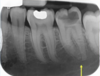

is the following periapical pathology or not?

yes

83

yes - root filled - PDL isnt continuous - lamina dura isnt continuous